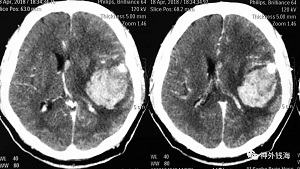

箭头所示为动脉瘤,悬挂于大脑中动脉主干上,瘤颈较宽,载瘤动脉远端通畅良好。

动脉瘤已经破裂,颞叶内有大量血肿。